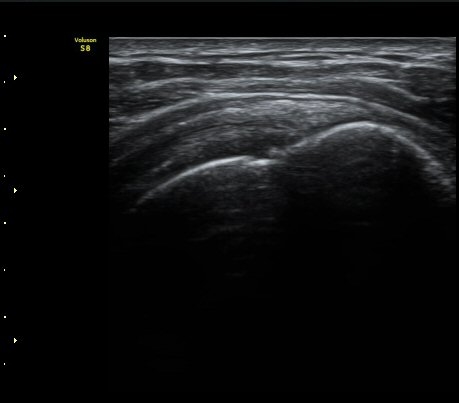

ÃÊÀ½ÆÄ °Ë»ç

ÀÌµÎ¹Ú±Ù°Ç È¾´Ü¸é°Ë»ç¿¡¼­ ƯÀÌ ¼Ò°ßÀ» º¸ÀÌÁö ¾ÊÀ½(»çÁø 1, 2).

±Ø»ó°Ç Á¾´Ü¸é°Ë»ç¿¡¼­ ±Ø»ó°Ç ÆÄ¿­Àº º¸ÀÌÁö ¾ÊÀ¸³ª »ó¿Ï°ñ ´ë°áÀý°ú °ñµÎ ÀÌÇàºÎÀ§¿¡¼­

ÇÇÁú°ñ ¿¬°á ¼Ò½Ç°ú ¹Ì¼¼ÇÑ °ñÆíÀÌ °üÂûµÊ(»çÁø 3, 4, 5).

±Ø»ó°Ç Ⱦ´Ü¸é°Ë»ç¿¡¼­ ±Ø»ó°Ç ±ÙÀ§ºÎ¿¡¼­´Â ƯÀÌ ¼Ò°ßÀ» º¸ÀÌÁö ¾ÊÀ¸³ª ±Ø»ó°Ç ¿øÀ§ºÎ¿¡¼­

ÇÇÁú°ñ ¿¬°á ¼Ò½Ç°ú ¹Ì¼¼ÇÑ °ñÆíÀÌ °üÂûµÊ(»çÁø 6, 7).